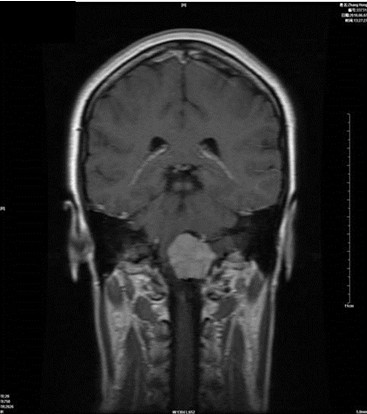

病例一:张**。女性,52岁。查体发现枕骨大孔区占位入院。临床诊断:枕骨大孔区腹侧脑膜瘤。术式:远外侧入路。术后病理脑膜瘤。

术前

术后